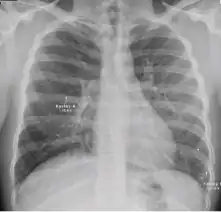

Chest x-ray showing nodular densities with distinct borders and no surrounding airspace opacification, with a reduction in the space occupied by the upper lobe.